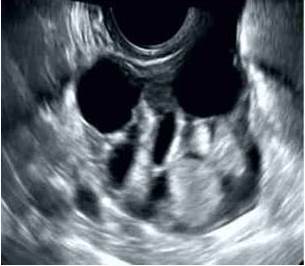

La ecografía pélvica mostró tumor sólido en ovario derecho que medía 8 cm x 5 cm x 4 cm, multilocular con líquido en cavidades quísticas irregulares y área sólida, lisa y redondeada con proyecciones papilares con flujo sanguíneo interno significativo sin evidencia de ascitis (Figura 1).

La sintomatología está caracterizada por la detección de tumoración ovárica, dolor abdominal, ascitis (alrededor de un tercio de los casos), alteraciones menstruales y, ocasionalmente, síndrome de Meigs (1). Menos del 5 % de los casos presentan evidencia clínica de hipertiroidismo. Los hallazgos de imágenes son inespecíficos. La evaluación por ecografía y tomografía computada muestran tumor complejo, superficie multilobulada con múltiples áreas sólidas-quísticas. Su diámetro puede variar entre 3 cm - 10 cm (5). Las características en las imágenes de resonancia magnética incluyen múltiples áreas intra-quísticas con baja intensidad de señal en imágenes ponderadas en T2 e intensidad de señal intermedia en imágenes T1, hallazgos que podrían indicar la presencia de tejido tiroideo. Un hallazgo común en la ecografía Doppler es el hallazgo de flujo sanguíneo en el centro del tumor, probablemente relacionado al tejido tiroideo altamente vascularizado comparado con otros tejidos avasculares presentes en los teratomas comunes. La gammagrafía con 131I es útil para en el diagnóstico de tejido tiroideo hiperfuncionante e intratumoral al demostrar mayor absorción del radionucleido (6).